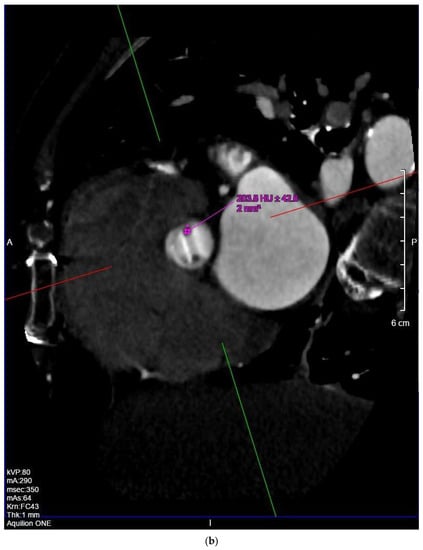

Female, 44 y/o, affected by mitral valve (MV) dysplasia (parachute valve with double medioposterior papillary muscle) and subaortic stenosis caused by a fibromuscular ring, underwent subaortic membrane resection and septal myectomy in 1989. Due to worsening exertional dyspnea and persistence of subaortic stenosis, a St. Jude Regent 17 mm was implanted in 2006 (40 y/o) with improvement of her physical condition. In the last 2 years, TTE detected a progressive increase of the intraventricular gradient with LV hypertrophy (maximum speed, 4.1 m/s, maximum/median gradient: 64/39 mm Hg). TEE performed in May 2020 showed normal excursion of the prosthesis’ leaflets and confirmed severe subaortic stenosis (speed: 5.5 m/s, maximum/median gradient: 120/63 mm Hg) (Supplementary Video S2). New subaortic membrane formation (SAM) was suspected but not clearly detected by TEE. MDCT provided accurate 3D reconstructions of the LV outlet tract (LVOT) with a better topographic assessment of the new SAM and its surrounding structures. The SAM was located 7 mm below the aortic prosthetic annulus, with the maximum thickness of 5 mm and hemicircumferential extension along the interventricular septal surface. This information was crucial to guide surgical excision of the SAM (Figure 2a,b).

Figure 2.

Long-axis (a) and short-axis (b) MPR focusing on the subaortic membrane (arrow) located 7 mm below the aortic annulus, with the maximum thickness of 5 mm and hemicircumferential extension along the interventricular septal surface.

In case 2, MDCT confirmed the presence of a subaortic membrane (SAM), which is one of the most frequent causes of subaortic stenosis. MDCT, due its better accuracy compared to US [18], was able to provide accurate 3D morphoanatomic information about the size, locations and extent of the fibromuscular bulge, the knowledge about which is a fundamental requirement to plan a surgical intervention [19], especially in this complicated patient affected by Shone complex.